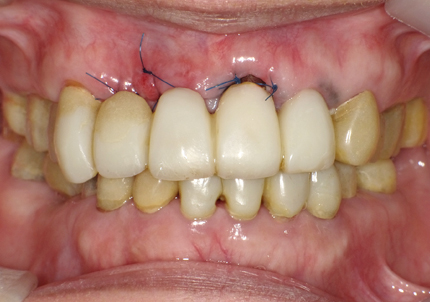

22.最終補綴物完成・装着口腔内写真(2021年1月)

23.自然な形態のインプラント歯頚部

適切な治療計画と治療技術を有することで、このような自然な形態のインプラント歯頚部を形成することができます。